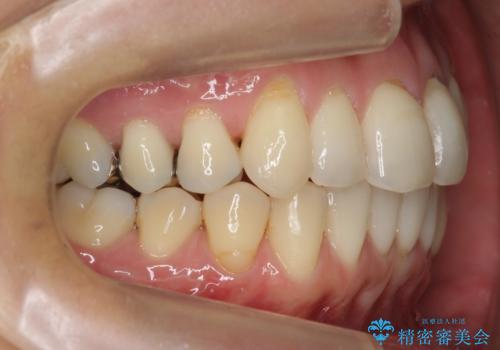

埋まっている奥歯を引っ張り出す インビザライン矯正

埋まっている奥歯を並べることで、その後ろの倒れ込んだ歯を整直させることができました。

上下とも非抜歯で並べています。

また、左上の変色した前歯はセラミックでやりかえを行なっています。

埋まっていた歯をしっかり引っ張り出すことができ、また、前歯の見た目も非常に良くなりました。